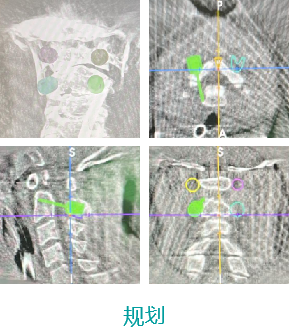

еӨ©зҺ‘IIи„ҠжҹұжүӢжңҜвҖ”йўҲжӨҺжүӢжңҜ

- дёҠдёҖзҜҮпјҡеӨ©зҺ‘IIи„ҠжҹұжүӢжңҜвҖ”иғёи…°жӨҺжүӢжңҜ 2022-01-19